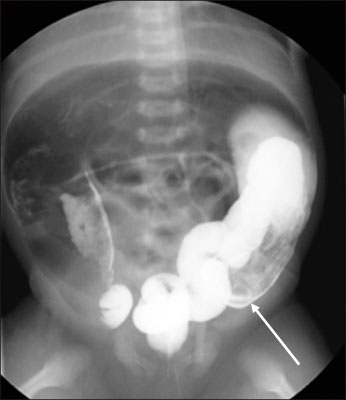

Fig. 1

Full-term 52-day-old boy with total colonic aganglionosis. False-positive transition zone (arrow) is noted at the descending colon (case 3).

Fig. 1 Full-term 52-day-old boy with total colonic aganglionosis. False-positive transition zone (arrow) is noted at the descending colon (case 3).